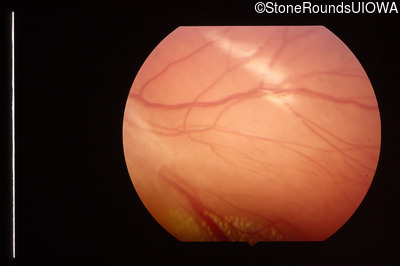

Fundus Photography - Left - 20/25 +1

Exemplar